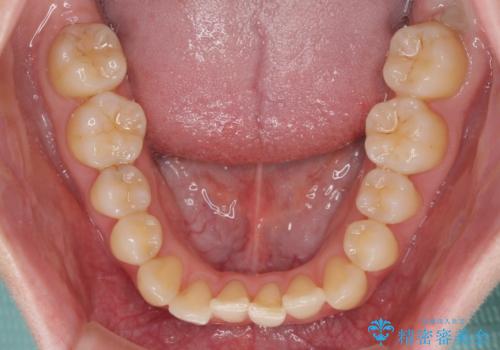

- ちょっとしたデコボコを整えたいとのことで来院された患者様です。

歯列不正は軽微であったため、インビザライン・ライトにより、費用を抑えて矯正治療を行うこととしました。

上下前歯の捻れが改善され、患者様には大変満足していただきました。